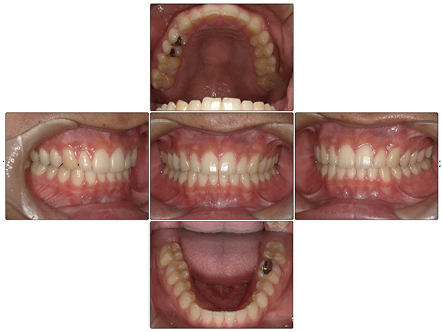

お口の中全体の写真

Before

お口の中全体の写真Before

患者の症状

上の前歯がすきっ歯なのが気になるということで矯正治療の相談をされた方です。

上の前歯の出っ歯以外にも上下の前歯に叢生を認め、咬合関係のズレも認めました。

上のすきっ歯は矯正治療前よりも閉鎖され、前歯が全体的に整って綺麗な歯並びとなりました。